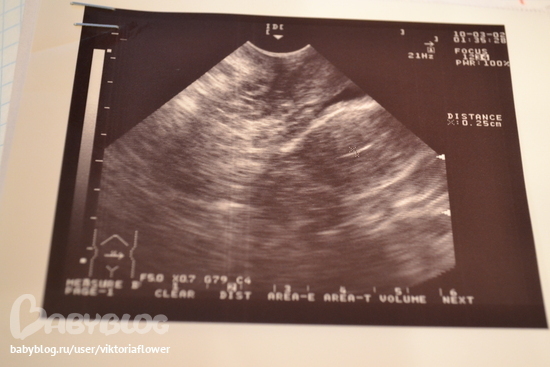

на второй картинке с лева, выше

Москва

это единственное что напоминает мне плодное яйцо